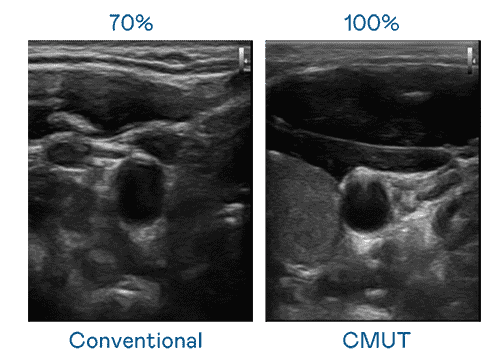

CMUT 技术是一种用电容式微机电元件来产生超音波讯号的技术。。。。与传统 PZT 压电式技术相比,,,,CMUT 频宽增加 30%,,更宽频的超音波讯号让影像解析度大幅提升,,,是实现高影像品质医疗超音波扫描、、、促进精准医疗发展的关键技术。。。。

大频宽带来超清晰影像

超音波影像的解析度高低,,,,首先取决于探头能发出的讯号频宽。。赏金国际 CMUT 可提供高清晰的超音波讯号,,,提供高频宽、、、、高灵敏度、、影像纹理细节更高的超音波影像,,,协助医护人员缩短影像判读时间及利用精准的医疗影像进行诊断。。。。